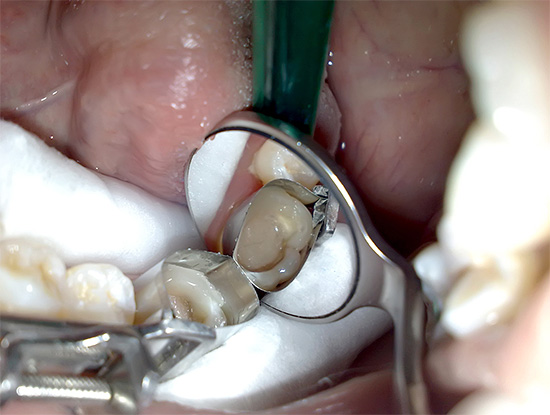

- Isolamento dei denti con un cassettone prima della preparazione o dell'uso di rulli di cotone sterili prefabbricati o pre-ritorti durante il riempimento e il riempimento del canale.

- Dissezione della cavità cariata e rimozione meccanica della dentina "sporca" infetta e pigmentata con trattamento farmacologico con antisettici (clorexidina, perossido di idrogeno).

- Divulgazione della bocca del canale.

- Il passaggio dei canali radicolari con file (speciali "aghi" intra-canale con bordi taglienti), seguiti dall'espansione e dalla formazione di una forma conica del diametro desiderato. Durante la procedura, dai canali viene effettuata la lisciviazione obbligatoria di polpa residua, pus, segatura sporca dalle pareti, ecc. L'odontoiatria moderna ha diversi metodi di "lavaggio" dei canali, ma la lavanda a getto con soluzione di ipoclorito di sodio si è diffusa con la polpite cancrenosa e altri tipi.